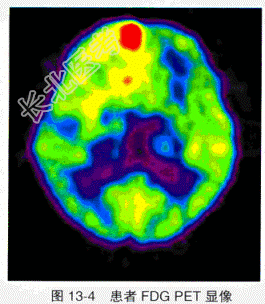

- 单项选择题患者,女性, 65岁。右额顶星形胶质细胞瘤术后并放疗15年后,CT示原肿瘤部位有增强。FDG PET显像见彩图13-4, 诊断是

E、肿瘤复发